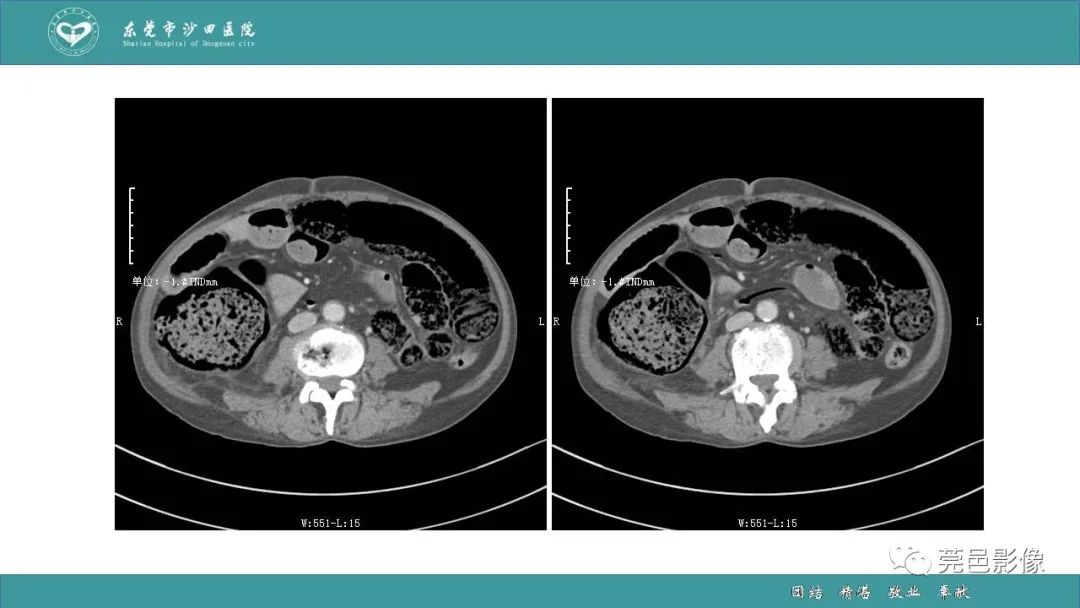

1例肠缺血坏死伴门静脉积气的CT诊断